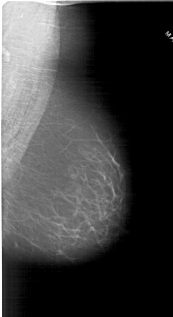

A_1800_1.RIGHT_MLO

RIGHT_MLO LINES 6016 PIXELS_PER_LINE 3271 BITS_PER_PIXEL 12 RESOLUTION 43.5 NON_OVERLAY